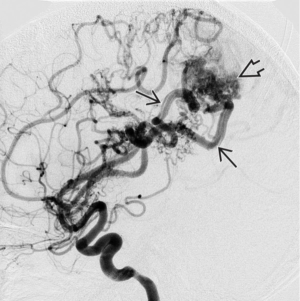

Demystifying AVMsByViktor Szeder, MD, PhD, MSC, FSVIN,David Kimball, MDJuly 7th 2022Risk assessment and management of brain arteriovenous malformations in pregnancy.